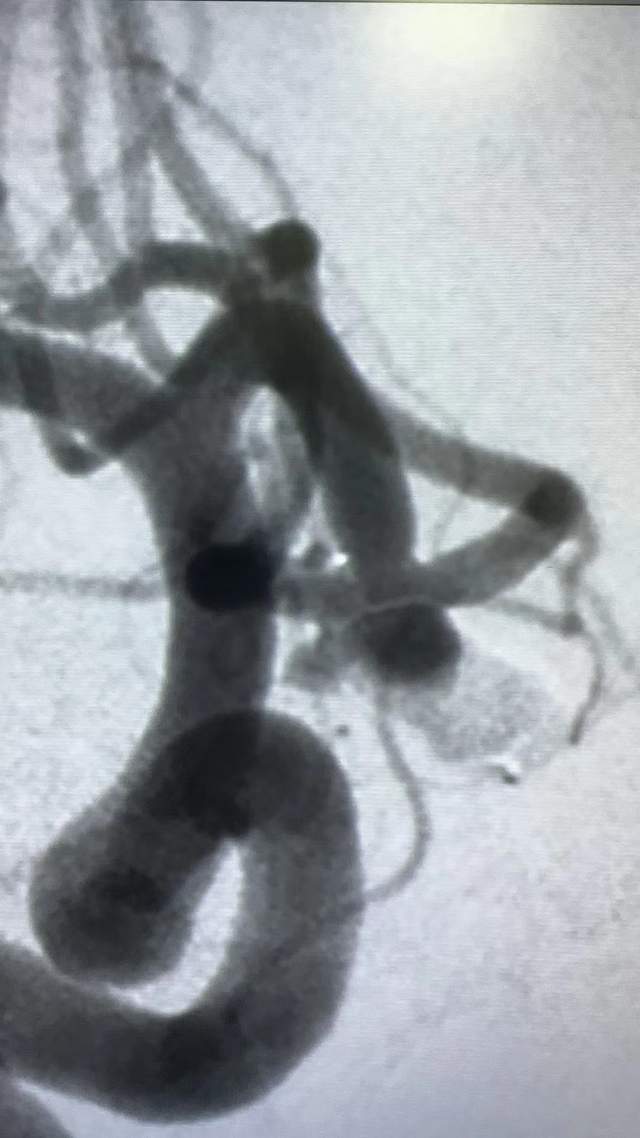

术后图片

术后动脉瘤腔造影剂滞留明显,子囊未显影,颅内血管通畅。